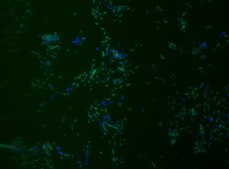

• Visualize, identify, and isolate Akkermansia muciniphila cells.

• Observe native A. muciniphila cell populations in diverse microbiome environments.

• Specific, sensitive, and robust identification of A. muciniphila in bacterial mixed population.

Fluorescent In Situ Hybridization technique (FISH) is based on the hybridization of fluorescent labeled oligonucleotide probe to a specific complementary DNA or RNA sequence in whole and intact cells.Microbial FISH allows the visualization, identification, and isolation of bacteria due to recognition of ribosomal RNA also in unculturable samples. FISH technique can serve as a powerful tool in the microbiome research field by allowing the observation of native microbial populations in diverse microbiome environments, such as samples from human origin (blood3 and tissue4), microbial ecology (solid biofilms5 and aquatic systems6) and plants7. It is strongly recommended to include positive and negative controls in FISH assays to ensure specific binding of the probe of interest and appropriate protocol conditions. We offer positive (MBD0032/33) and negative control (MBD0034/35) probes, that accompany the specific probe of interest. Akkermansia muciniphila probe specifically recognizes Akkermansia muciniphila cells. Akkermansia muciniphila is a gram negative, oval shaped, non-motile, non-spore forming strictly anaerobic bacteria.8 A. muciniphila inhabits the gastrointestinal tracts of more than 90% of adults and constitutes 1 to 4% of the fecal microbiota.9 It is one of the top 20 most abundant species detectable in the human gut.10 The mucus layer of the human intestine is a niche which is colonized by specific bacteria such as A. muciniphila. A. muciniphila can degrade mucin, a key mucus component, using the enzymes sialidase and fucosidase, and utilize it as a source of carbon and nitrogen.11 Consequently, the host produces additional mucus while the bacterium produces oligosaccharides and Short Chain Fatty Acids (SCFAs) that can be utilized by the host and trigger the immune system. An additional protective effect of the SCFA is stimulation of mucus-associated microbiota growth, that serves as a barrier against penetration of pathogens to intestinal cells.9,12 It was found that A. muciniphila abundance in the gut was correlated to a healthy intestine and inversely correlated to many disease conditions.11 In comparison to healthy controls, A. muciniphila levels were low in patients with intestinal disorders, such as inflammatory bowel disease (IBD), but also in other conditions, such as autism, atopy, and obesity.11,13-16 Therefore, the level of A. muciniphila was suggested to serve as a biomarker for healthy intestine.17 A. muciniphila is a promising potential probiotic that can be administrated for the treatment of diseases such as, colitis, metabolic syndromes, immune diseases, and cancer.10 FISH technique was successfully used to identify A. muciniphila with the probe in various samples such as pure culture (as described in the figure legends18), fecal samples19-21, gut lumen content22, appendix samples23, cecum content and tissue24,25 and colon tissue26. The probe can also be used for FISH coupled with flow cytometry (FCM-FISH)19,20,21, and FISH combined with Raman microspectroscopy